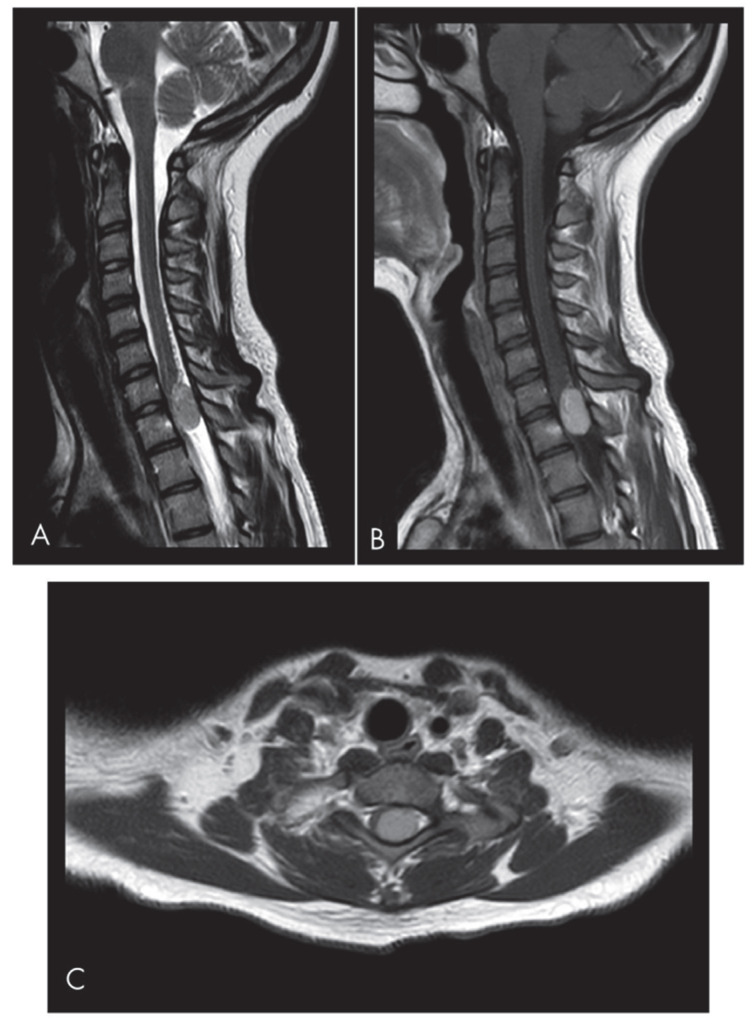

Solitary fibrous tumors (SFTs) are rare mesenchymal neoplasms of fibroblastic origin. In this study, we report a rare case of cervical SFT in a pediatric patient, a rare phenomenon since the incidence is particularly rare in pediatric patients according to the literature. Typical radiological features of the lesion may lead to misdiagnosis. Image study and immunohistochemistry are crucial for its correct diagnosis. Their imaging characteristics often resemble meningiomas or schwannomas, making differential diagnosis challenging. Immunohistochemical markers such as CD34 and STAT6 remain essential for definitive diagnosis.